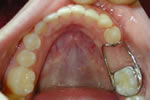

band loop space maintainer

erupting tooth